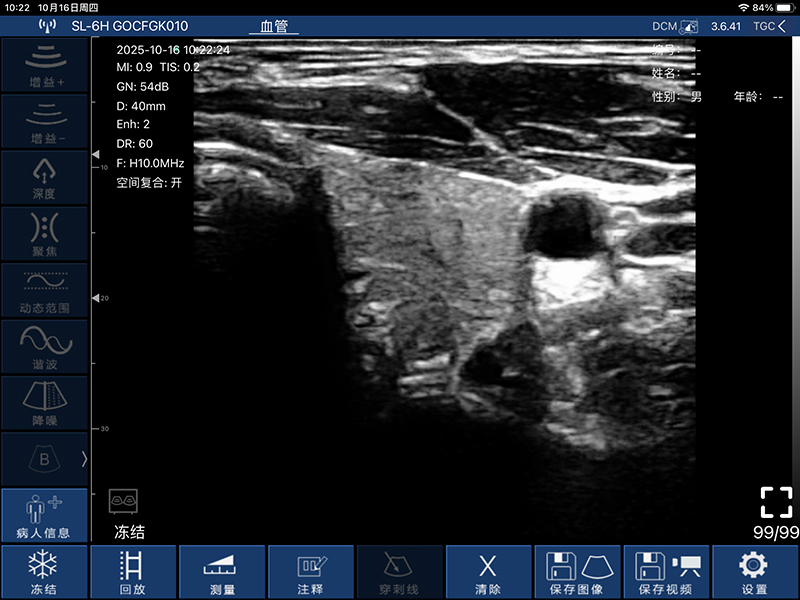

• 扫描方式:电子阵列扫描

• 探头频率:7.5/10MHz

• 扫描深度:20-100mm,可调

• 显示模式:B、B/M、Color、PW、PDI

• 穿刺辅助功能:平面内穿刺引导线功能,平面外穿刺引导与血管自动测量功能